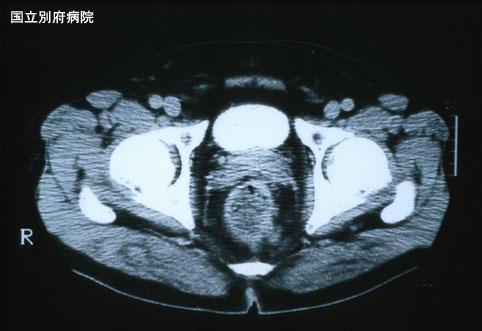

Melanoma Maligno del Recto acompañado de metástasis al pulmón (Caso presentado por el Hospital Nacional de Beppu)

[Image-ID:3127]

Melanoma Maligno/

colon/recto

TAC

ss(a1)